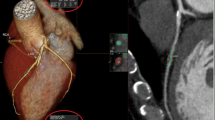

According to the criteria of North American symptomatic carotid endarterectomy trail (NASCET)[10], carotid and cerebrovascular arteries were divided into 40 segments including common carotid artery (CCA), carotid bifurcation (CB), external carotid arteries, internal carotid arteries (ICA) (C1-C7), extracranial vertebral artery (eVA), intracranial vertebral artery (iVA), basilar artery (BA), anterior cerebral artery (A1, A2), middle cerebral artery (M1, M2), posterior cerebral artery (P1, P2), anterior communicating artery (ACoA), and posterior communicating artery (PCoA). These segments were also divided into 3 categories, including extracranial arteries (CCA, CB, CA, C1, and eVA), intracranial ICA (C2-C7), and intracranial arteries(iVA, BA, A1, A2, M1, M2, P1, P2, ACoA, and PCoA). Only segments with a diameter >1.5 mm (as measured on the MDCT angiogram) were included. The type of plaque was determined using the following classification proposed by Ballotta E et al.[11]: 1) non-calcified plaques, plaques having lower density less than 50 HU; 2) calcified plaques, Plaques with a mean attenuation of 130 HU or greater; and 3) mixed plaques, plaques with a mean attenuation of 50-129 HU (Figure 1). A grade of stenosis was assigned for each chosen segment: grade 0 for normal or no observable plaque, grade 1 for diameter stenosis <30%, grade 2 for 30%–69% diameter stenosis, grade 3 for plaques with 70%–99% diameter stenosis, and grade 4 for 100% occlusion (Figure 1)[10]. Finally, it was determined whether the plaque was obstructive or not, using a threshold of 70% luminal narrowing. Each vessel was analyzed on at least two imaging planes, one parallel and one perpendicular to the course of the vessel, and the vessel diameters were measured on perpendicular to the vessel course. For each patient the number of diseased segments, type of plaque and degree of stenosis were determined and recorded.

MDCT identified 183 (93.8%) and 12 (6.2%) patients with and without cerebrovascular disease. A total of 1056 segments with plaque were identified. With regard to plaque constitution, 450 (42.6%) of the plaques were classified as non-calcified plaques, 192 (18.2%) as mixed and 414 (39.2%) as calcified plaques (Figure 2). Among these segments containing plaques, mild stenosis was observed in 562 (53.2%) segments, moderate stenosis in 291 (27.6%) segments, severe stenosis in 170 (16.1%) segments, and occlusion in 33 (3.1%) segments. In general, eight hundred and fifty-three (80.8%) plaques showed non-obstructive and 203 (19.2%) plaques showed obstructive.